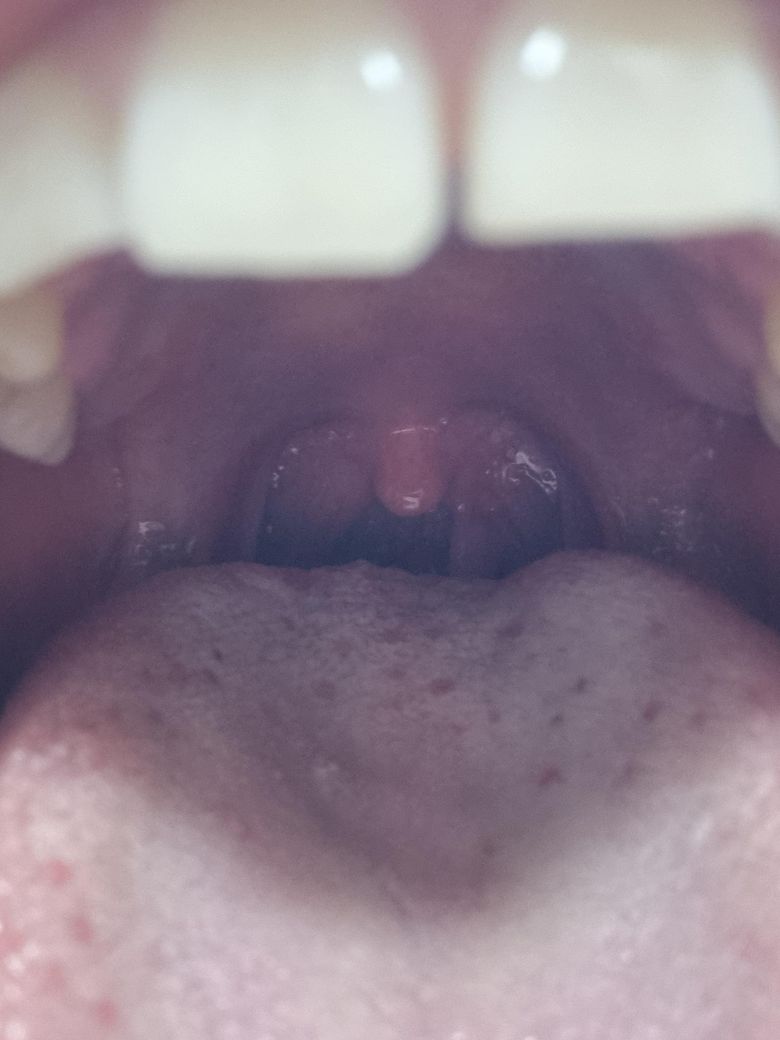

1년전부터 목젖옆에 혹이 생겼는데 점점 커지더니 이물감이 느껴지고 고개를 젖히거나 기침할때 달랑거리는게 보입니다. 이비인후과 방문해야할까요?

• 1번 째 사진

• 사진상으로는 목젖(구개수) 옆에 매달린 형태의 돌출 병변이 보이며, 형태상 가장 흔하게는 양성 점막 병변(유두종, 섬유성 폴립 등)이 우선 의심됩니다. 말씀하신 것처럼 “달랑거림”이 느껴지는 경우는 실제로 줄기(stalk)가 있는 폴립성 병변에서 흔합니다.

병태생리적으로 이런 병변은 만성 자극(기침, 역류, 음주, 흡연 등)이나 바이러스성 원인으로 점막이 증식하면서 생길 수 있습니다. 1년 이상 지속되면서 크기가 커졌고, 이물감이 생겼다는 점은 단순 염증성 부종보다는 구조적 병변 가능성을 더 시사합니다.

임상적으로 중요한 점은 다음입니다. 대부분은 양성이지만, 크기 증가, 출혈, 통증, 삼킴 장애, 목소리 변화가 동반되면 감별이 필요합니다. 특히 구강·인두 부위는 육안만으로 확진이 어려워 내시경 확인이 필요합니다.

결론적으로 현재 상태는 반드시 이비인후과 진료가 필요한 상황입니다. 진료에서는 후두내시경으로 정확한 위치와 형태를 확인하고, 필요 시 간단한 절제 및 조직검사를 시행하게 됩니다. 이런 병변은 외래에서 비교적 간단히 제거 가능한 경우가 많습니다.

당장 응급 상황으로 보이진 않지만, “떨어질 것 같은 느낌”은 실제 탈락보다는 움직임에 의한 착각인 경우가 대부분이므로 자가로 건드리거나 제거 시도는 피하시는 것이 안전합니다.